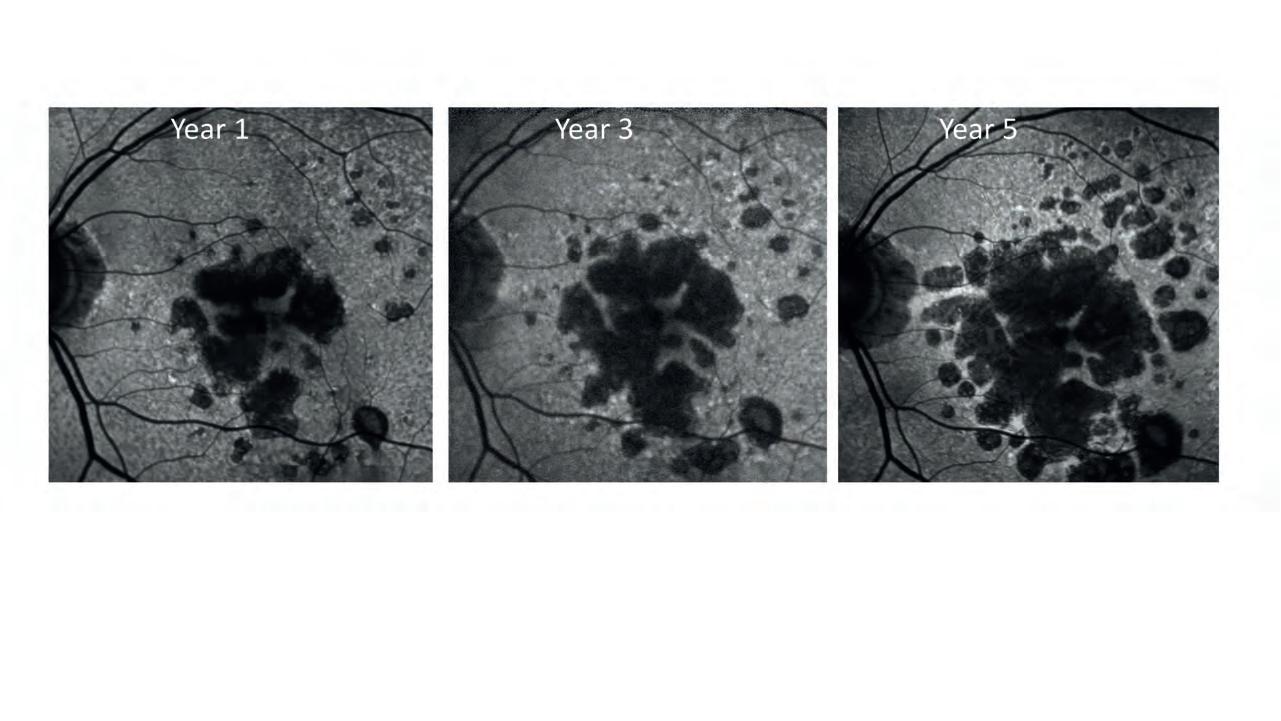

Geographic atrophy

Prof Robyn Guymer on the final hurdles towards an approved therapy and how local eyecare professionals can prepare.

Retinal risk

Around half of people with late-stage disease age-related macular degeneration will have geographic atrophy (GA), with estimates suggesting five million people have GA worldwide. Page 69